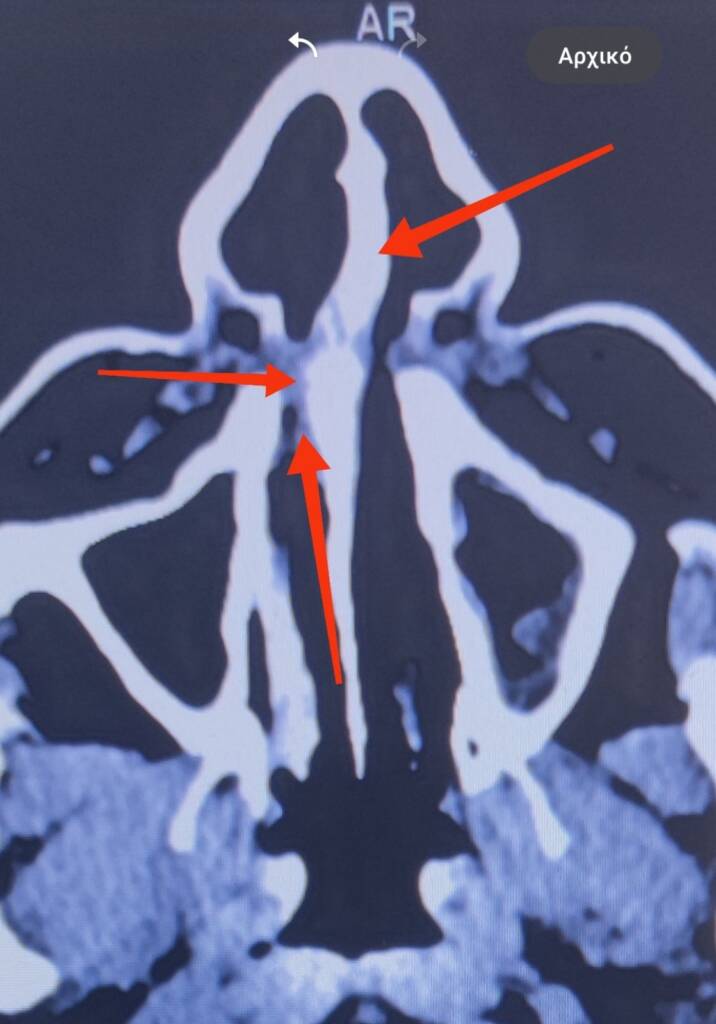

Η πιο απλή ΩΡΛ εξέταση δηλαδή  η πρόσθια ρινοσκόπηση θα καταδείξει το πρόβλημα. Η χρήση οπτικών ινών και ενδοσκοπίων θα αναδείξει τις λεπτομέρειες και τις ακριβείς θέσεις του προβλήματος. Η απλή ακτινογραφία όπως και η αξονική τομογραφία θα αποδώσει το πρόβλημα όπως και πιθανές παράπλευρες παθολογικές καταστάσεις  στα  ιγμόρεια , στο ρινοφάρυγγα, ρινικούς  πολύποδες, κύστεις κλπ.